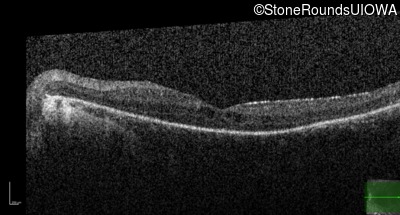

Optical Coherence Tomography - Right - 10/40 sc

Exemplar / OCT Stack